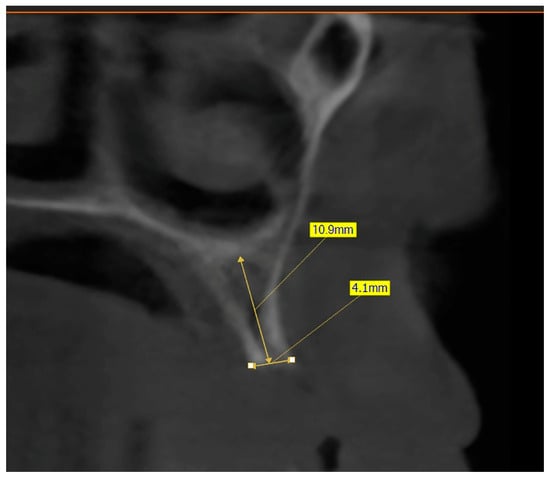

Figure 1. Bone measurement on a cross-sectional image—CBCT (Green X™ 12®, Vatech, Prague, Czechia).

Figure 2. Bone density around a virtually placed dental implant—CBCT (Green X™ 12®, Vatech, Prague, Czechia).

The preoperative plan included a detailed history, clinical examination, and analysis of 3D CBCT images. Detailed measurements of bone height and width at the sites of the future implants (at the level of planned position of implant platform), as well as bone density, were performed on cross-sectional CBCT images (Figure 1 and Figure 2) by an investigator who was not involved in the surgical procedure. Prior to the surgery, an oral rinse of chlorhexidine digluconate solution 0.2% (Hibideks DAP®, Galenika, Beograd, Serbia) was administrated to all the patients for 1 min.